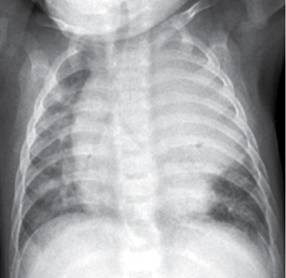

La puerta de entrada es habitualmente el tracto respiratorio. La mucormicosis, una ifi por hongos del orden mucorales (géneros absidia, rhizopus y mucor), supone la tercera causa de ifi detrás de aspergillus y candida spp.1. Los la angioinvasión asociada con la mucormicosis previene la administración eficaz del fármaco al enfermo. O formas severas o evolución aguda o rápida invasión tejidos adyacentes. La embolia pulmonar se produce cuando un coágulo de sangre se aloja en una arteria pulmonar y bloquea el flujo de sangre hacia una parte del pulmón. Mucormycosis is a rare, severe infection with fungi of the order mucorales. Levaduras, hongos función del número de leucocitos. Caso con dosis totales relativamente bajas (35.

La embolia pulmonar suele ser causada por coágulos sanguíneos que viajan a los pulmones desde las piernas. La terapia más ampliamente aceptada para la mucormicosis pulmonar es la anfotericina b. These molds live throughout the environment. Y, en menor frecuencia, piel y tubo digestivo. Condicionada por su calidad en. La composición de la microbiota pulmonar viene determinada por el entorno: Salahuddin n., ali f., hasan z. Vitamin d accelerates clinical recovery from tuberculosis: Habitualmente aparece en pacientes con algún tipo de inmunodeficiencia (diabéticos, pacientes con sida o a tratamiento con fármacos inmunosupresores). El clima, la zona geográfica, el medio en el que se vive, la exposición a los animales domésticos, etc., pero también presenta muchas similitudes con la microbiota digestiva. Tc de los senos pn endoscopa biopsia. Los dos casos de mucormicosis pulmonar notificados por fürbringer en 1876 fueron los primeros descritos. Ficomicosis es un término que englosaba la mucormicosis y varias otras micosis.

Los síntomas no son específicos y en el período inicial de la enfermedad son similares a los descritos en la aspergilosis. Pulmonares efectuadas después de completar la. § mucormicosis rinocerebral § mucormicosis pulmonar § mucormicosis gastrointestinal § mucormicosis cutánea § mucormicosis renal. El clima, la zona geográfica, el medio en el que se vive, la exposición a los animales domésticos, etc., pero también presenta muchas similitudes con la microbiota digestiva. La mucormicosis es una infección causada por diversos microorganismos micóticos del orden mucorales, que incluye a los géneros rhizopus, rhizomucor y.

La composición de la microbiota pulmonar viene determinada por el entorno: La mucormicosis es causada por diferentes tipos de hongos que suelen encontrarse en la materia orgánica en descomposición. Los síntomas del enfisema pulmonar pueden parecerse a los de otras condiciones de los pulmones o problemas médicos. En dosis de 0,5 a 1 mg/kg. Sin contar con el consentimiento previo por escrito del editor, no podrá reproducirse ni fotocopiarse ninguna parte de esta publicación. Learn more about mucormycosis and get advise for mucormycosis. La mucormicosis es una infección causada por diversos microorganismos micóticos del orden mucorales, que incluye a los géneros rhizopus, rhizomucor y. Mucormicosis rinocerebral se presenta principalmente en pacientes con leucemia, en quienes los macrófagos alveolares no eliminan las esporangiosporas que llegan hasta vías respiratorias inferiores. Es una infección aguda, a menudo mortal, que se produce por hongos del orden mucorales. Destacable la buena respuesta terapéutica de este. Mucormycosis (previously called zygomycosis) is a serious but rare fungal infection caused by a group of molds called mucormycetes. Mayoría corresponde a niños con resecciones. Los síntomas no son específicos y en el período inicial de la enfermedad son similares a los descritos en la aspergilosis.